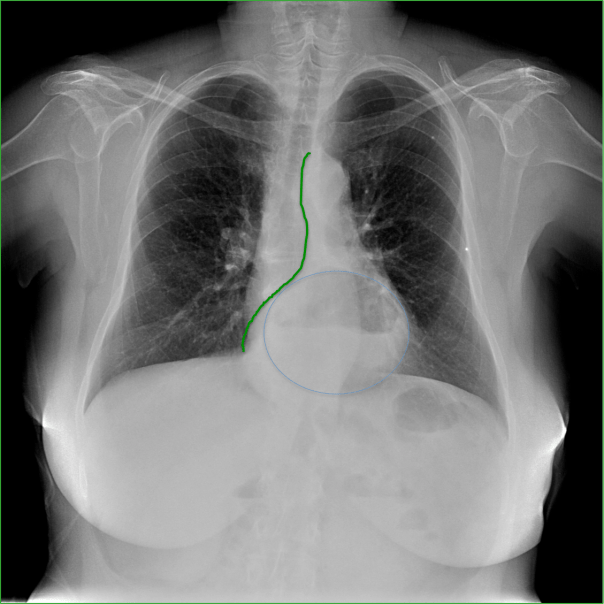

CASO: Operada de esofaguectomia y reconstrucción con coloplastia hace 3 meses. Sintomas de neumonía.

Hallazgos:

- De inicio llama la atención una densidad practicamente total del todo el hemitórax izquierdo, lo cual podría hacernos pensar que estamos ante una posible neumonía.

- Sin embargo el tórax está no está bien centrado, observar como la clavícula izquierda se encuentra casi en la mitad del pulmón, por tanto lo que vemos blanco es el mediastino ya que el tórax está rotado.

CENTRAJE:

El correcto centraje se determina comprobando que las extremidades internas de ambas clavículas equidistan de las apófisis espinosas vertebrales.

Mismo paciente, al cual esta vez se le ha tomado una radiografía en PA y en sedestación. Observar como las clavículas están equidistantes a las apófisis espinosas y como ha desaparecido el velamiento del pulmón izquierdo.

Por otra parte, paciente presenta una cardiomegalia y un discreto ensanchamiento del mediastino es probable relación con cambios postquirúrgicos.